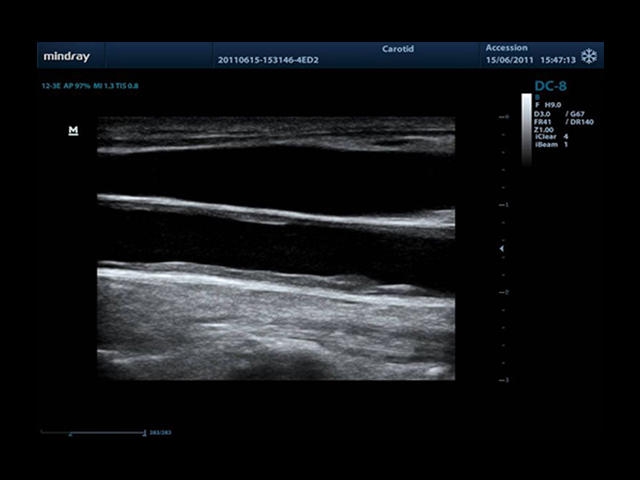

• Auto IMT Package - измерения и анализ толщины комплекса интима-медиа (КИМ) сонной артерии.

Mindray DC-8 Exp оснащен новым поколением датчиков с увеличенным количеством элементов и инновационной технологией "3T". Это позволяет достичь высокой детализации и качества изображения. Благодаря новейшей технологии iFlow, можно визуализировать даже самые мелкие сосуды и кровеносные пути.

Сверхширокополосная нелинейная обработка изображений снижает визуальные шумы на 30% по сравнению с другими системами. Технология iClear позволяет устранить зернистость изображения, а iBeam (технология пространственного компаундинга) обеспечивает высокое качество сканирования органов и тканей под различными углами.